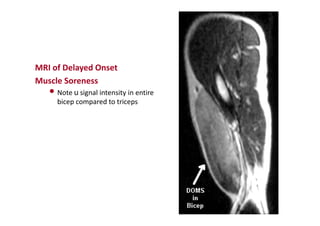

Delayed Onset Muscle Soreness

MRI of Delayed Onset

Muscle Soreness

• Note u signal intensity in entire

bicep compared to triceps